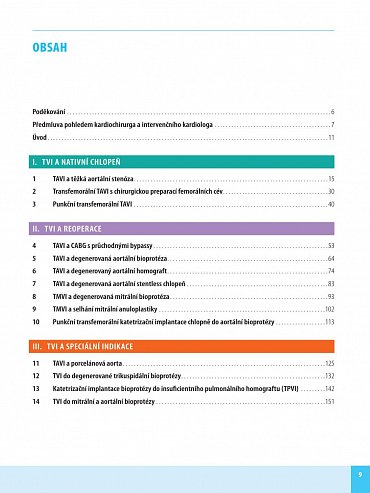

Transkatétrová implantace chlopní (TVI) je minimálně invazivní výkon umožňující náhradu poškozené srdeční chlopně - aortální nebo mitrální. Preferuje se zejména u pacientů s vysokým rizikem komplikací chirurgického výkonu na otevřeném srdci. Kniha obsahuje velký počet pečlivě vybraných kazuistik se stručným schématem diagnostického postupu, diferenciální diagnostikou a technikou operace. Vlastní popis je doplněn množstvím zobrazovacích vyšetření a peroperačních fotografií, které umožní orientaci čtenáře a pochopení základních kroků diagnostiky a léčby.

Kniha Transkatétrová implantace chlopní v instruktivních kazuistikách je určena kromě kardiochirurgů rovněž kardiologům, kteří pečují o kardiochirurgické pacienty po operaci a často je na operaci připravují. Nejde přitom o monografii pro úzký okruh čtenářů, ale o praktickou příručku pro každodenní použití.